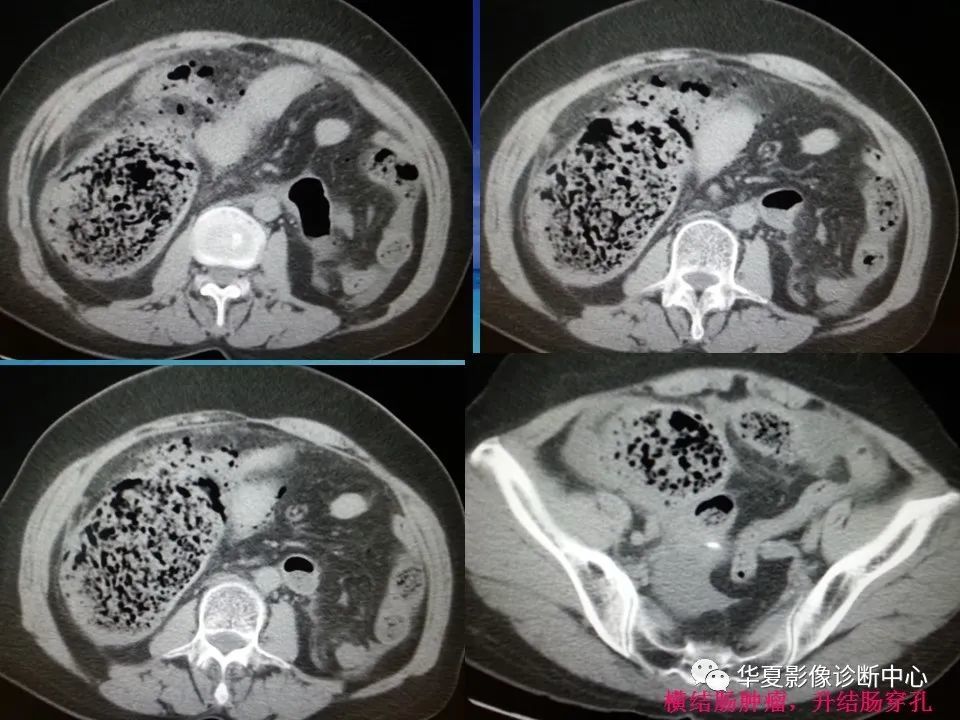

消化道穿孔ct影像大汇总看完印象深刻

消化道穿孔的ct诊断